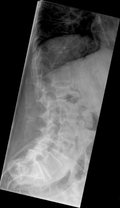

Для диагностики остеопороза используются рентгенография и денситометрия.

Рентгенологический метод исследования проводится на развернутой стадии развития заболевания.Развитие остеопороза оценивают зрительно по плотности изображения кости на рентгенограмме. Очаговый остеопороз представляет собой множество нечетко отграниченных участков разрежения костного вещества округло-овальной или многоугольной формы. При равномерном остеопорозе кость выглядит более прозрачной, костные перекладины истончены, общая картина губчатого вещества просматривается с трудом, а при резко выраженном процессе исчезает совсем.